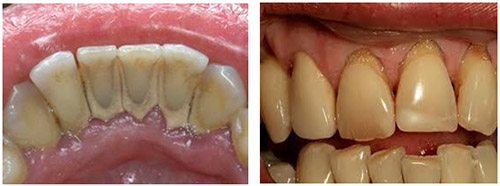

Кроме того, зубной камень может стать причиной неприятного запаха изо рта, изменения цвета зубов и кровоточивости десен, что создает значительный эстетический дискомфорт. В целом, контроль за количеством и качеством зубных отложений является важнейшим аспектом профилактики кариеса и заболеваний пародонта. На следующем рисунке представлено, как выглядит зубной камень.

Среди достоинств лазерной чистки зубов можно выделить: высокую эффективность, отсутствие боли, а также безопасность для зубной эмали и десен. Однако использование дорогостоящего лазерного оборудования приводит к высокой стоимости данной услуги. Кроме того, не все стоматологические клиники располагают таким оборудованием. Ниже представлены фотографии до и после процедуры удаления зубного камня.